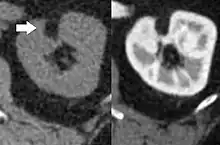

Three methods of scanning can detect angiomyolipomas: ultrasound, computed tomography (CT), and magnetic resonance imaging (MRI).[5] Ultrasound is standard and is particularly sensitive to the fat in angiomyolipomas, but less so to the solid components. However, accurate measurements are hard to make with ultrasound, particularly if the angiomyolipoma is near the surface of the kidney (grade III).[4] CT is very detailed and fast, and allows accurate measurement. However, it exposes the patient to radiation and the dangers that a contrast dye used to aid the scanning may itself harm the kidneys. MRI is safer than CT, but many patients (particularly those with the learning difficulties or behavioural problems found in tuberous sclerosis) require sedation or general anaesthesia, and the scan cannot be performed quickly.[3] Some other kidney tumours contain fat, so the presence of fat is not diagnostic. Distinguishing a fat-poor angiomyolipoma from a renal cell carcinoma (RCC) can be difficult.[6] Both minimal fat AMLs and 80% of the clear-cell type of RCCs display signal drop on an out-of-phase MRI sequence compared to in-phase.[7] Thus, a lesion growing at greater than 5 mm per year may warrant a biopsy for diagnosis.[3]